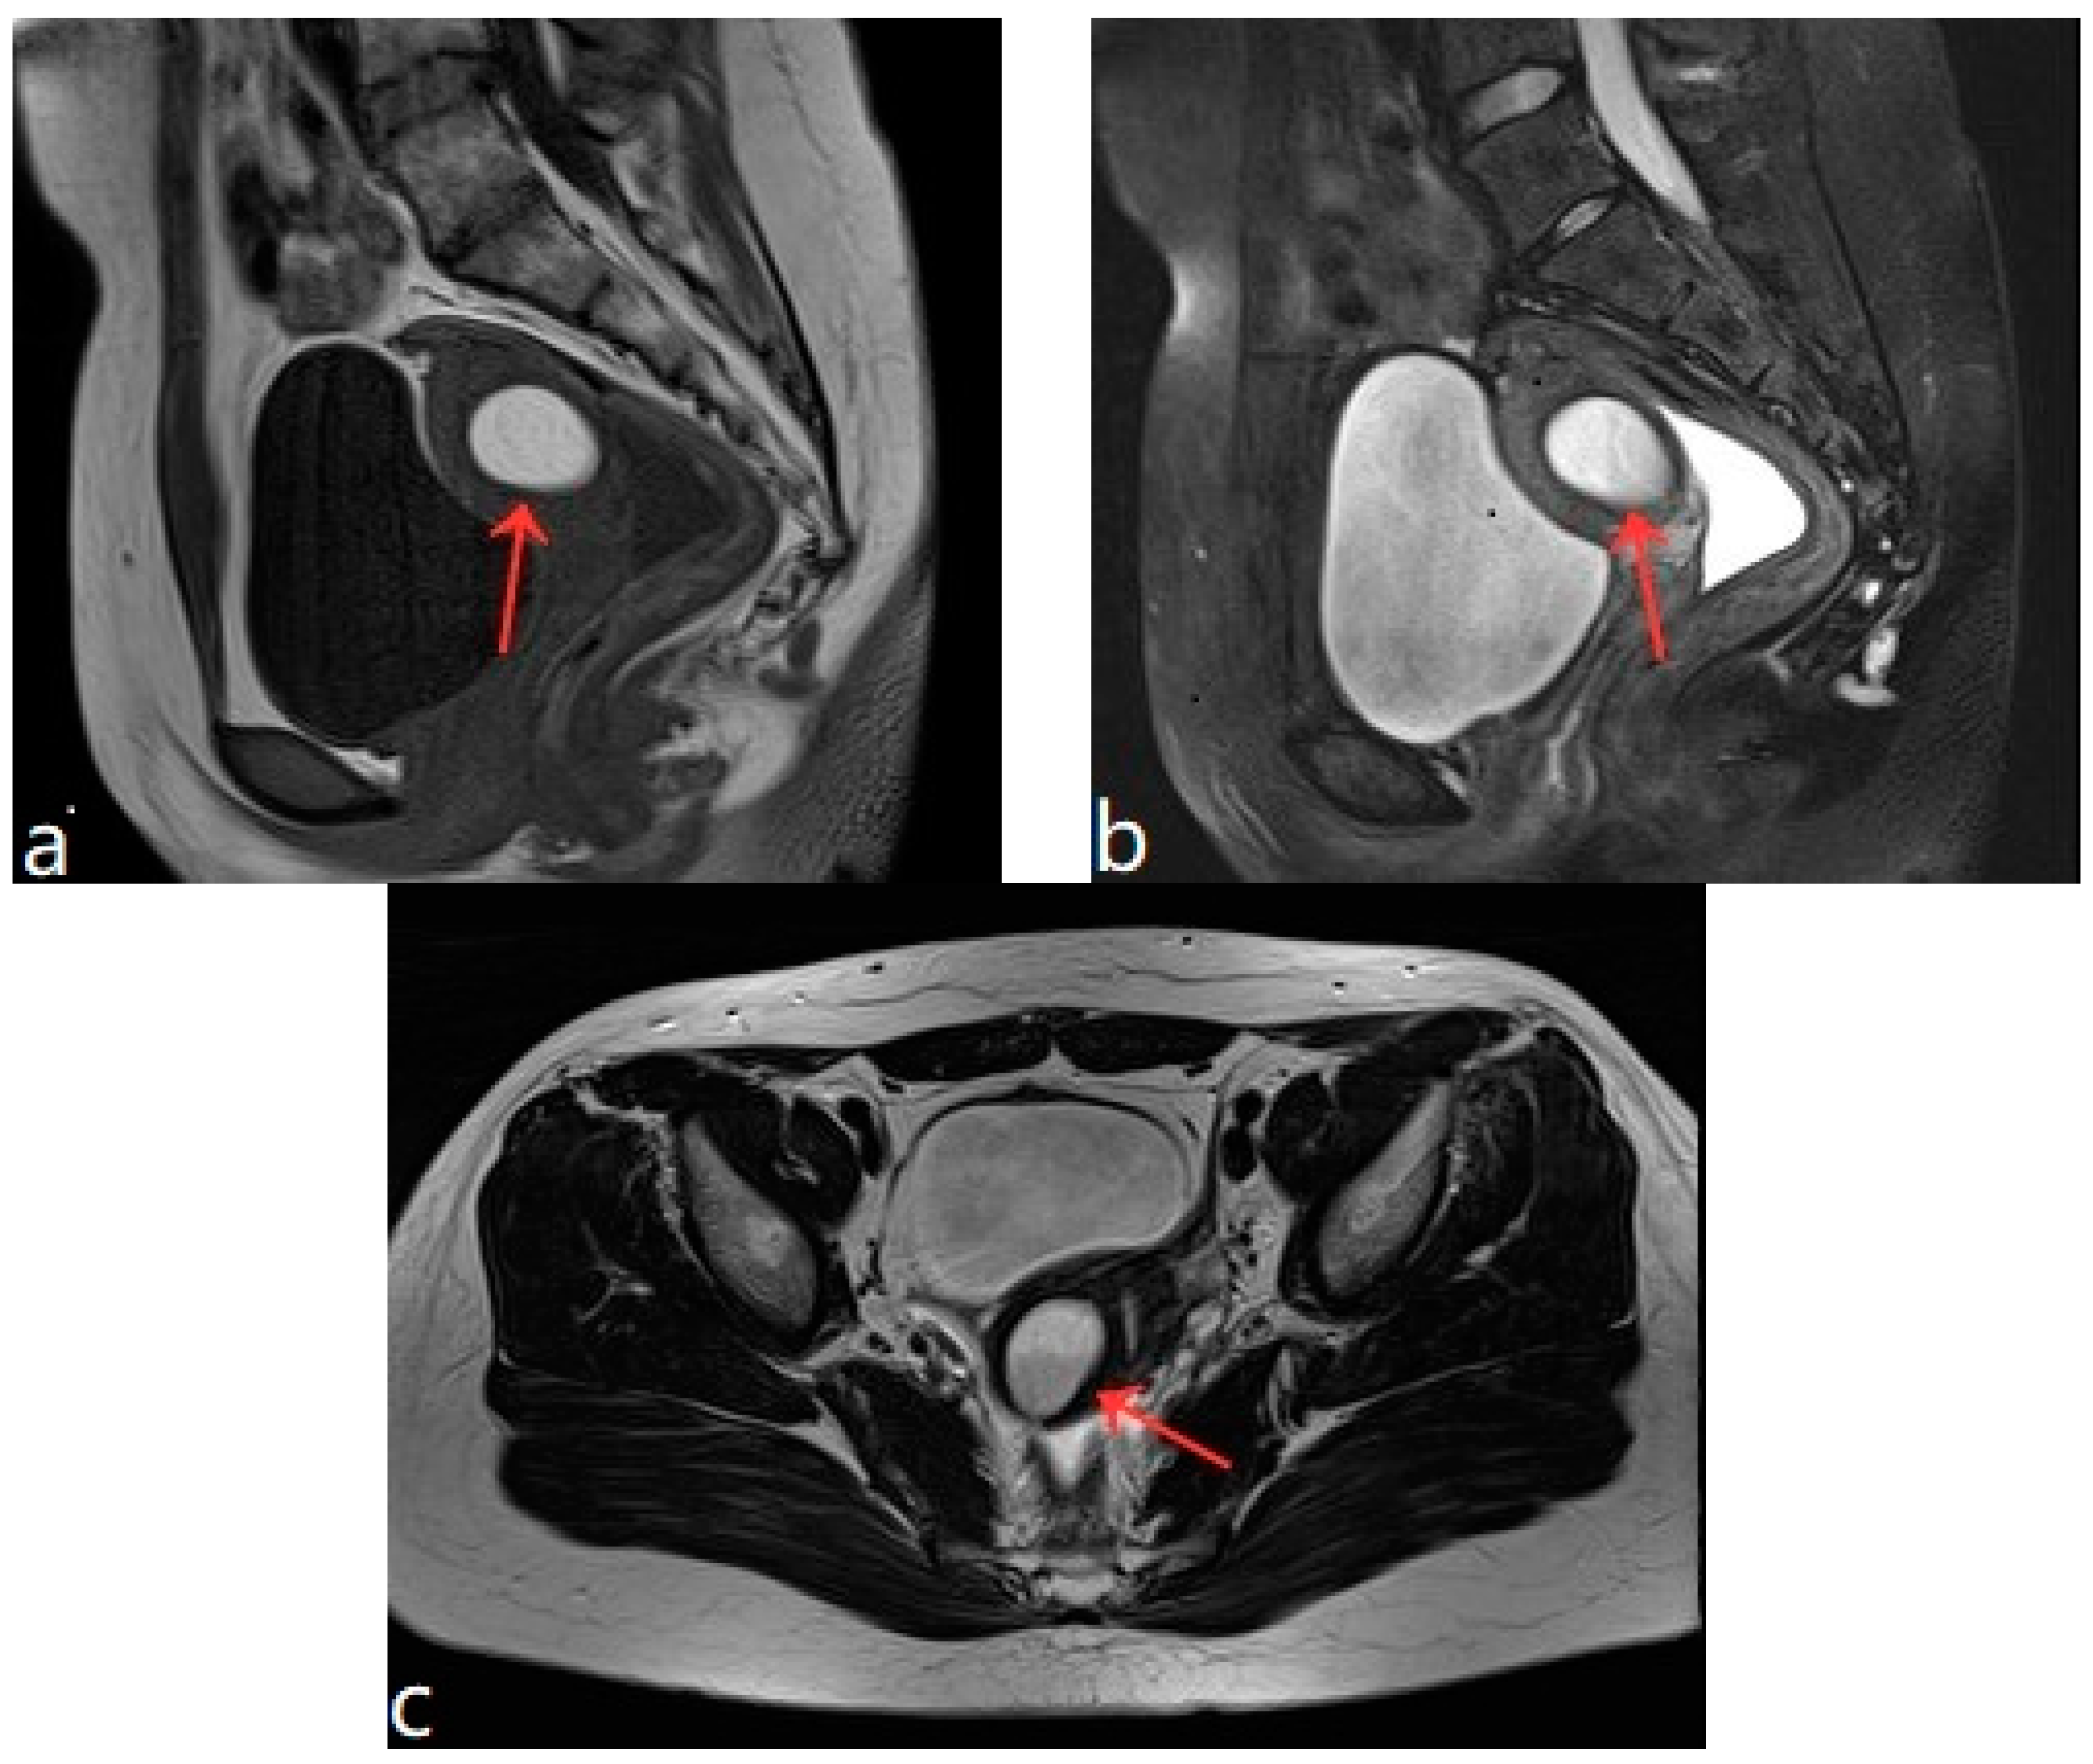

Figure 1.

(a–c) Pelvic MRI: sagittal TIWI sequence (a), sagittal T2WI fat suppression sequence (b), and axial T2WI non-fat suppression (c) showing a cystic lesion in the right posterior wall of the uterus with regular morphology, oval shape, and clear border (red arrows).